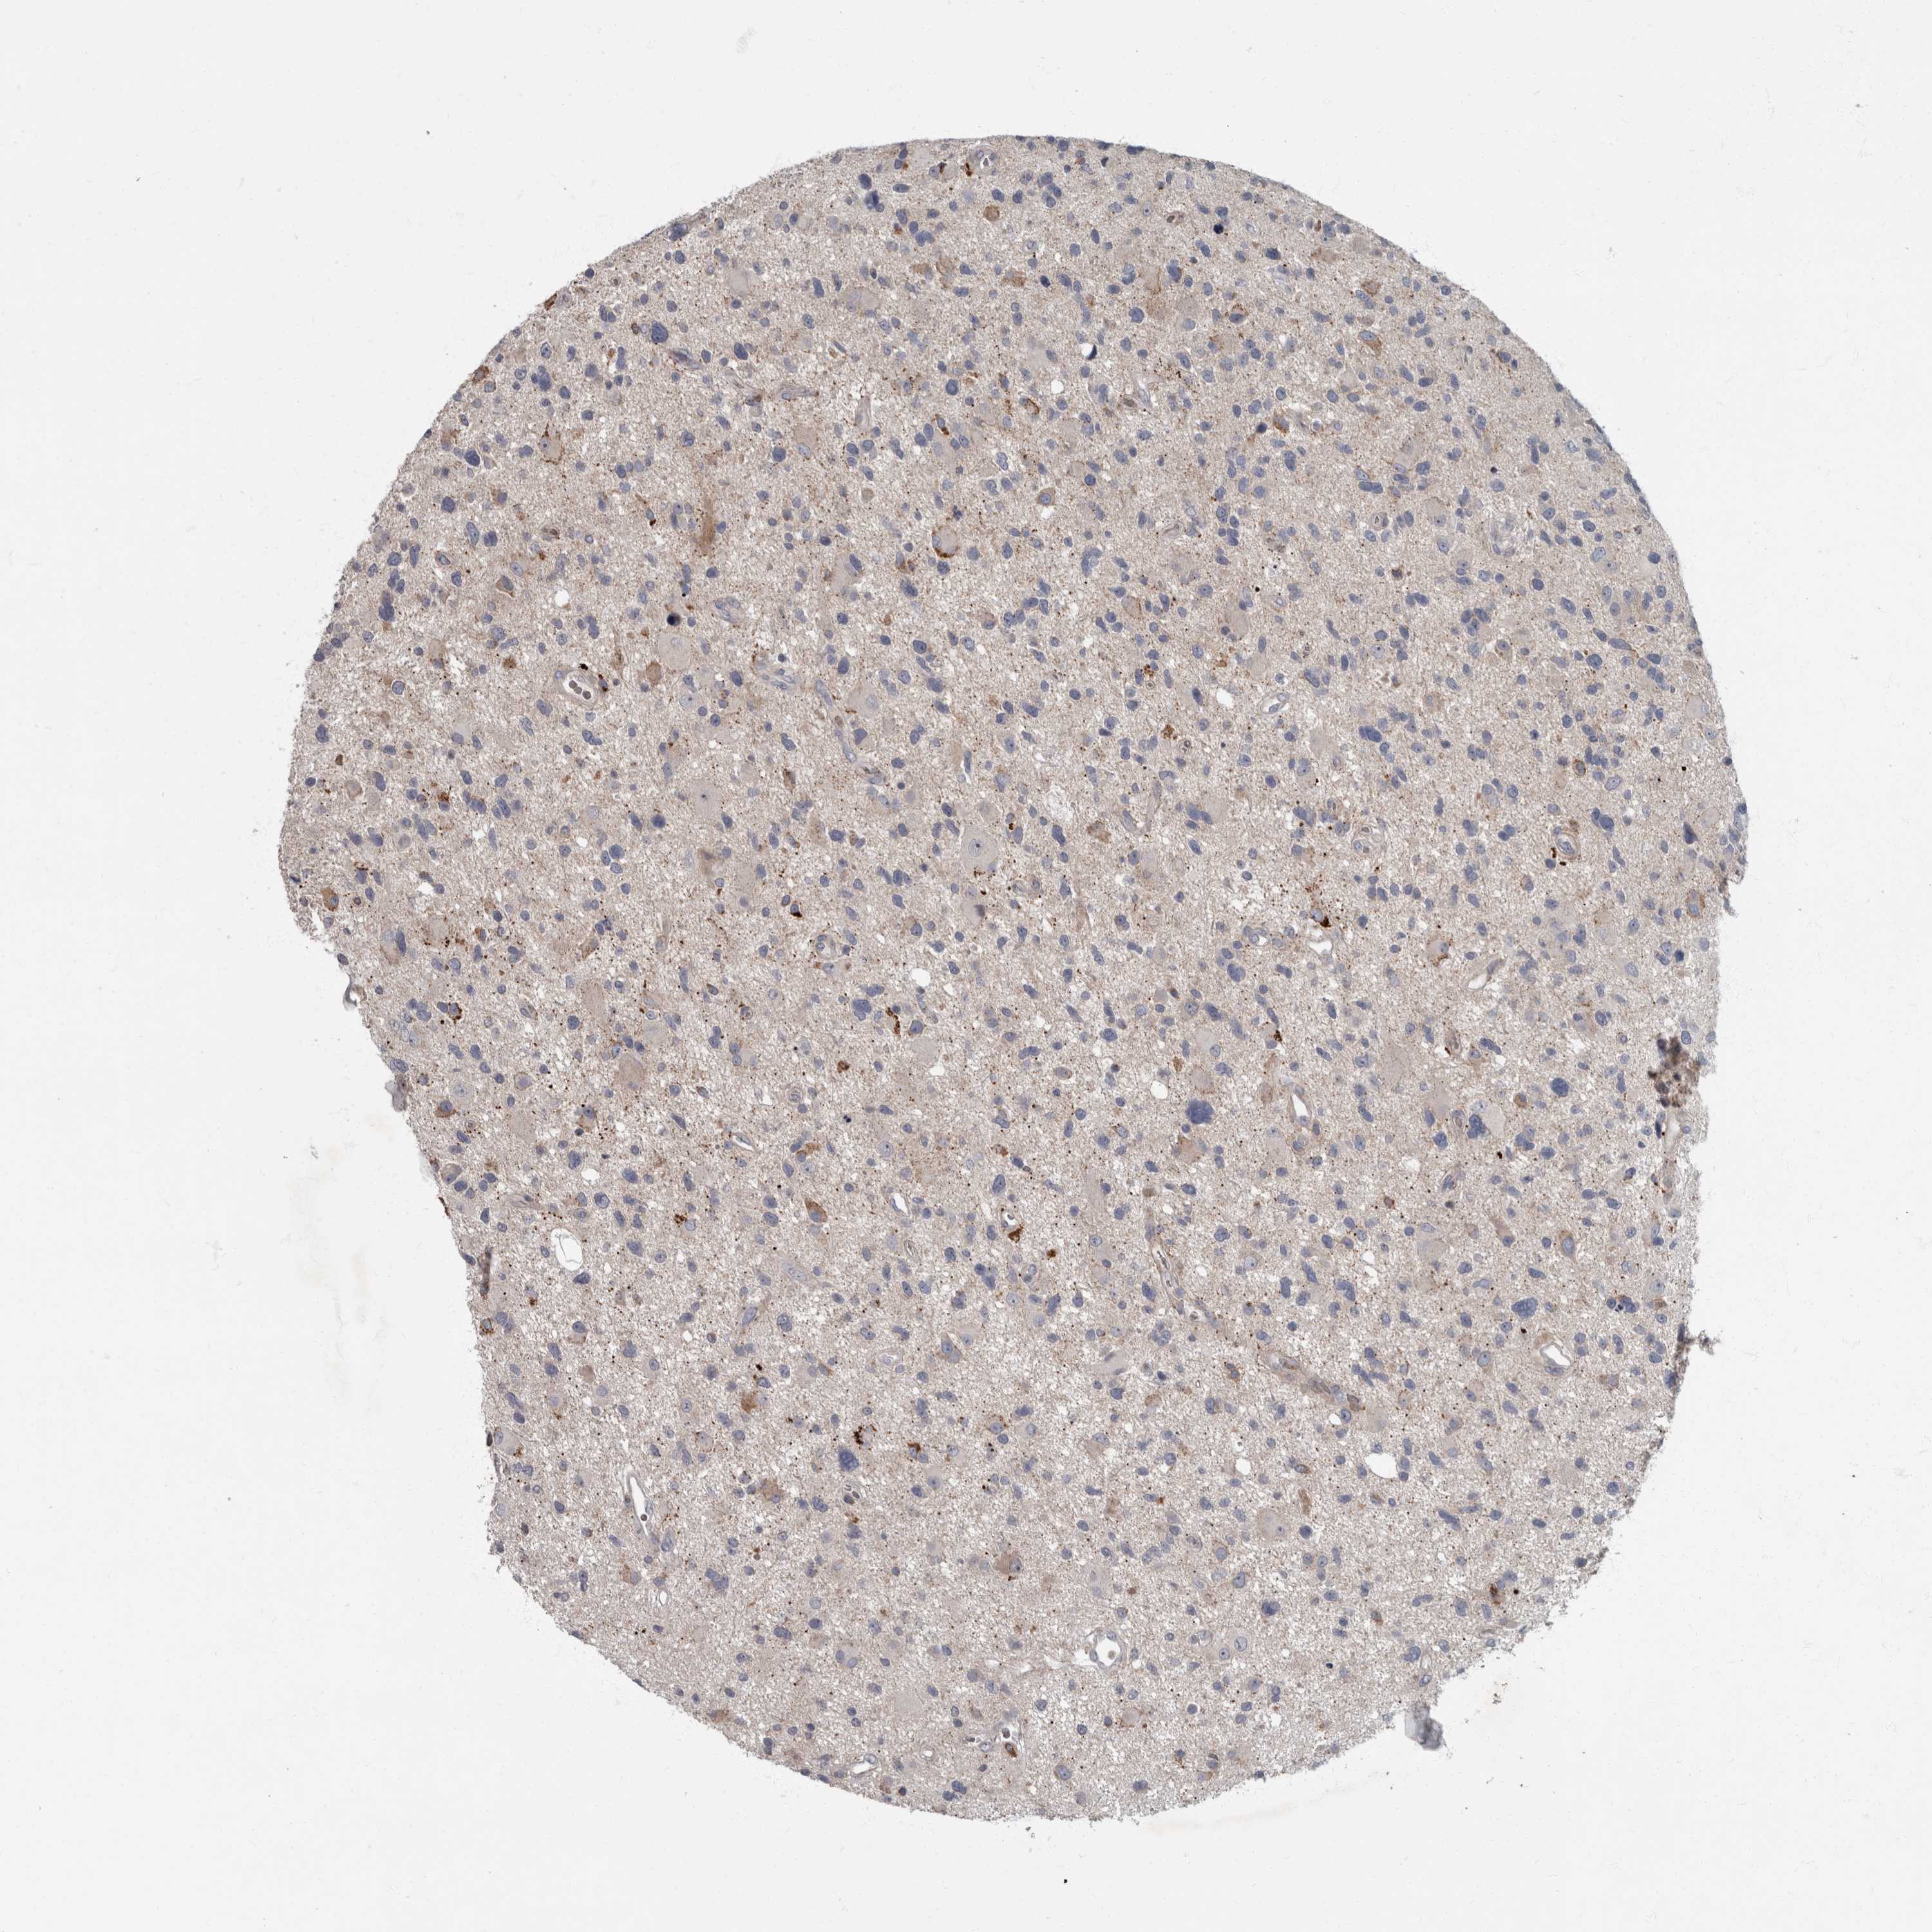

GLIOMA - Protein expressioni

A mouse-over function shows sample information and annotation data. Click on an image to view it in a full screen mode. Samples can be filtered based on level of antibody staining by selecting one or several of the following categories: high, medium, low and not detected. The assay and annotation is described here.

Note that samples used for immunohistochemistry by the Human Protein Atlas do not correspond to samples in the TCGA dataset.

Antibody stainingi

Antibody staining in the annotated cell types in the current human tissue is reported as not detected, low, medium, or high, based on conventional immunohistochemistry profiling in selected tissues. This score is based on the combination of the staining intensity and fraction of stained cells.

Each image is clickable and will lead to virtual microscopy that enables deeper exploration of all samples and also displays staining intensity scores, fraction scores and subcellular localization as well as patient and tissue information for each sample.

Antibody HPA027382

Antibody HPA061836

Staining

High

Medium

Low

Not detected

Intensity

Strong

Moderate

Weak

Negative

Quantity

>75%

75%-25%

<25%

None

Location

Nuclear

Cytoplasmic/membranous

Cytoplasmic/membranous,nuclear

Glioma, malignant, High grade

Glioma, malignant, Low grade